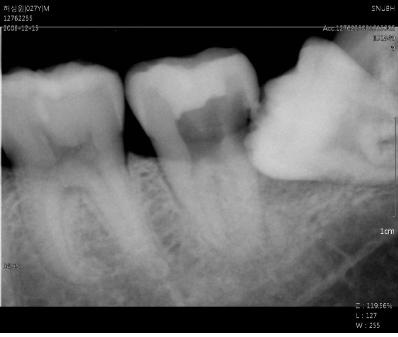

↑ [헬스조선]사진출처=분당서울대병원

또한 치아 상실시 사랑니를 옮겨 심을 수 있다는 장점도 있다. 치아가 손상되어 발치할 경우 바로 임프란트를 하는 것이 아니라 사랑니를 사용할 수 있다. 이렇게 하면 치아의 기능을 더 오래 유지할 수 있다. 따라서 사랑니가 났다면 우선 치과를 찾아 방사선 사진을 촬영한 후 구강 검사를 받고 검사 결과를 토대로 특별한 이상이 없는 경우라면 다른 치아처럼 잘 유지하는 것을 권한다.

하지만 미리 발치해 주는 것이 좋은 경우가 있다. 기형적으로 맹출하여(경사지게 맹출하거나 일부만 맹출한 경우) 앞의 어금니를 손상시키는 경우인데 이런 경우 전문의와 상담하여 유지할지 발치할 지 여부를 평가하는 것이 바람직하다.